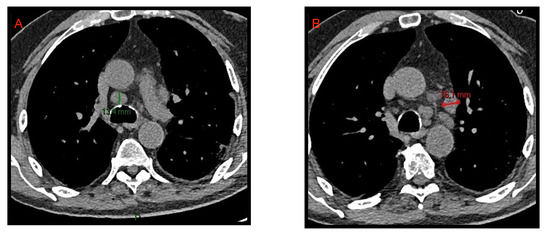

Figure 2. CT axial images of mediastinal lymphadenopathies. Enlarged lymph nodes with short axis of 13.4 mm and 16.1 mm are evident in the lower pre-tracheal space (A) and in the aorto-pulmonary window (B), respectively.

With the term “lymphadenopathy” we refer to mediastinal lymph nodes >10 mm and hilar lymph nodes >3 mm in short axis diameter. As already reported by Li et al. [8], and by Grassi et al. [9], lymphadenopathies are part of the acute COVID-19 manifestations even if they do not represent a specific and characteristic sign (Figure 2). Xiao Li et al. [10] reported that hilar and mediastinal lymph node enlargement was observed in 43.51% of patients with COVID-19 pneumonia. Their study suggested that enlarged hilar and mediastinal lymph nodes are associated with immune response and that patients with COVID-19 pneumonia have stronger immune response especially in moderate and severe conditions.